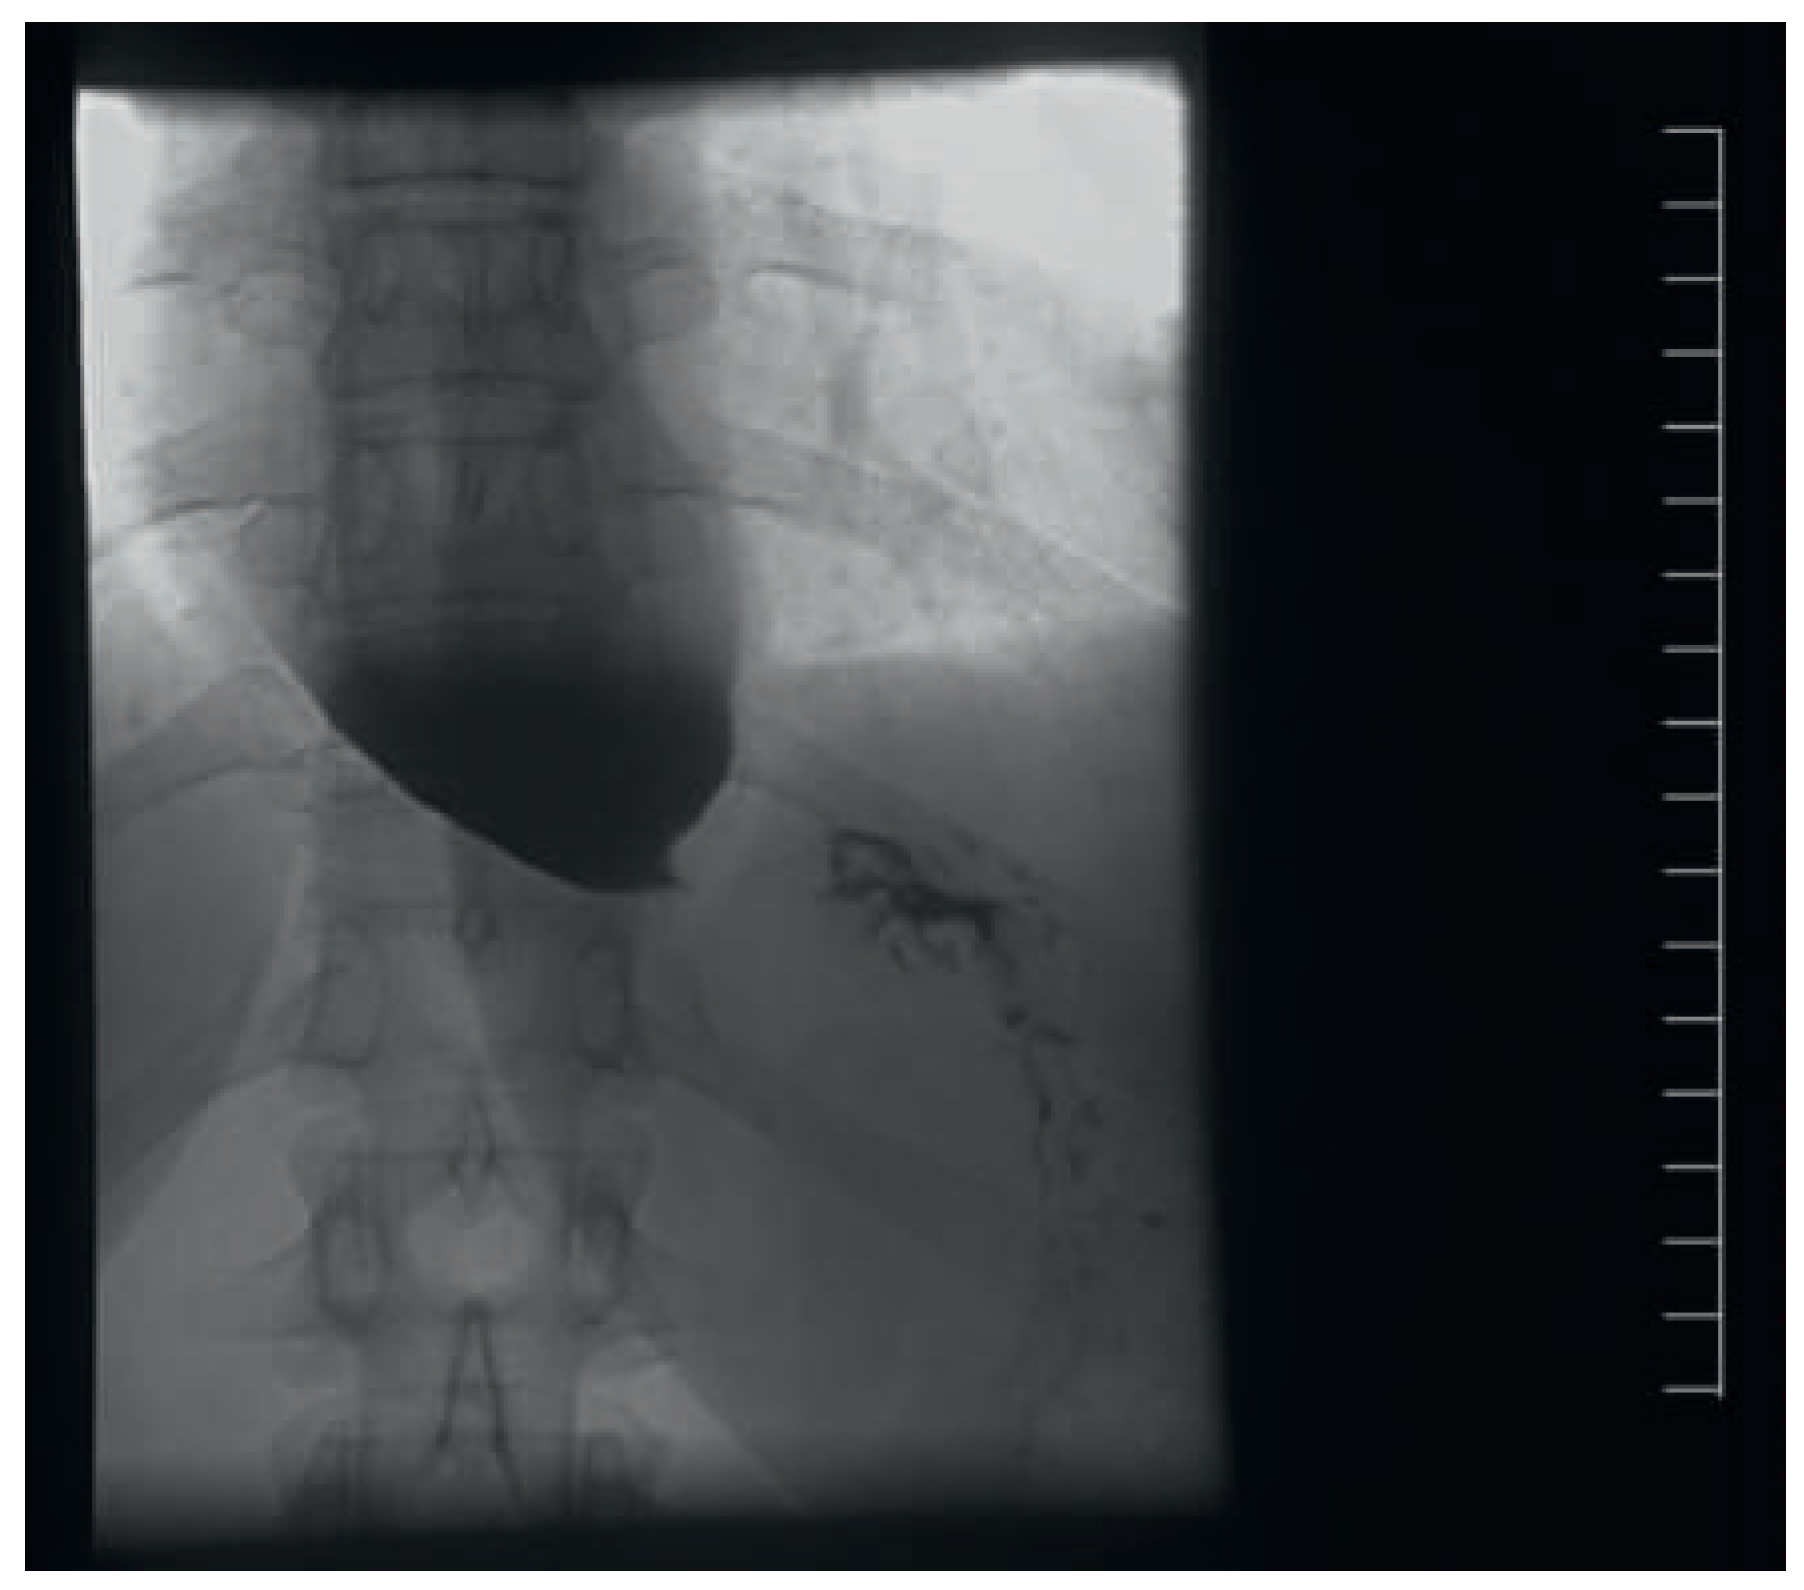

Abbildung 7. Ösophaguspassage (Ausschnitt auf Höhe gastroösophagealer Übergang) bei primärer Achalasie, mit Dilatation des distalen Ösophagus und Engstellung des Übergangs in den Magen.

Die primäre Achalasie ist eine weitere, oft verzögert diagnostizierte Entität mit dem Leitsymptom einer Dysphagie. Es handelt sich um eine ösophageale Motilitätsstörung, charakterisiert durch aufgehobene Peristaltik im tubulären Abschnitt und fehlende schluckinduzierte Erschlaffung des unteren Ösophagussphinkters [16]. Als Ursache wird eine durch virale Infekte getriggerte autoimmune Ganglionitis angenommen. Die Verdachtsdiagnose kann bereits radiologisch gestellt werden (Abb. 7); für eine definitive Diagnose ist aber in jedem Fall eine endoskopische Abgrenzung gegenüber sekundären Formen (wie z.B. Kardiakarzinom) und eine manometrische Bestätigung nötig. Therapeutisch stehen wahlweise mehrere endoskopisch-interventionelle Methoden oder die chirurgische Myotomie zur Verfügung. Kritisch für die TEE ist der Umstand, dass der untere Ösophagussphinkter dem Gerät einen erhöhten Widerstand entgegensetzt oder unter Umständen gar nicht passierbar ist. Im fortgeschrittenen Stadium ist der distale Ösophagus zudem dilatiert und siphonartig dekonfiguriert. Dies erschwert die Passage in den Magen zusätzlich und akzentuiert die Perforationsgefahr.